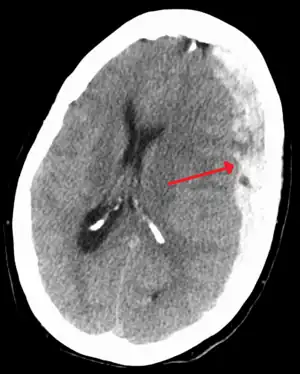

| Subdural hematoma as marked by the arrow with significant midline shift | |

A subdural hematoma (SDH) is when a collection of blood forms between the inner layer of the dura mater and the arachnoid mater of the meninges surrounding the brain.[2] Symptoms may include headache, confusion, personality change, and loss of consciousness.[1] Complications may include brain herniation and seizures.[2]